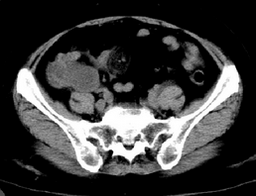

阑尾粘液腺癌

右侧下腹疼痛,二便常规正常,其他化验室检查无异常

手术病理

:

。